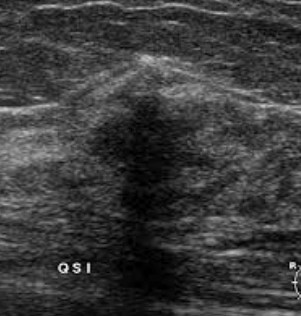

Gambar Ultrasonografi Payudara menunjukkan antara massa kistik (berisi cairan) dan padat

Kista Kompleks Payudara - menunjukkan kandungan padatan dan kistik (berisi cairan) campuran